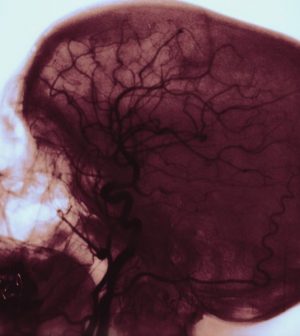

As the researchers explained, injecting heroin or other opioids can enable bacteria to get into the body. These germs then travel via the bloodstream to infect and inflame heart valves — a dangerous condition called infective endocarditis.

Once infective endocarditis occurs, clumps of infected tissue can break off and travel to the brain’s blood vessels and block them, triggering stroke.